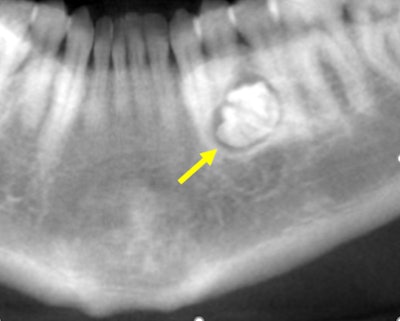

Figure 1: Reformatted CBCT panoramic film.

A hyperdense lesion (radiopaque) surrounded by a hypodense ring with very well-defined

borders. A distal extension of the lesion takes the form of a primitive root. The lesion is in the middle of the mandible. Tooth #21 is slightly mesially displaced. Initial resorption is observed at the distal third aspect of the root of tooth #21. The lesion is displacing apically the mental foramen.